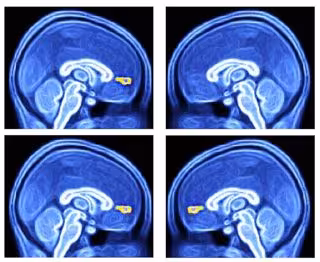

Científicos de la Escuela de Medicina Wake Forest han dado el primer paso en el desarrollo de una prueba objetiva que diagnostique el autismo. Usando resonancia magnética funcional (IRMf), el equipo pudo medir la respuesta de los niños autistas a las diferentes señales ambientales al visualizar una parte específica del cerebro involucrada en la asignación de valor a las interacciones sociales.

En su trabajo, el equipo probó la capacidad de respuesta de la corteza ventral medial prefrontal del cerebro (vmPFC) a las señales visuales que representaban una interacción social en niños diagnosticados con trastorno del espectro autista (TEA) en comparación con los niños con desarrollo típico (TD). El estudio incluyó a 40 participantes de edades entre los 6 y los 18 años: 12 tenían TEA y 28 eran TD.

Según el estudio, la respuesta promedio del vmPFC fue significativamente menor en el grupo de TEA que en el grupo de niños con desarrollo típico. Usar imágenes como un solo estímulo para capturar 30 segundos de datos de IRMf fue suficiente para diferenciar los grupos de TEA y TD.